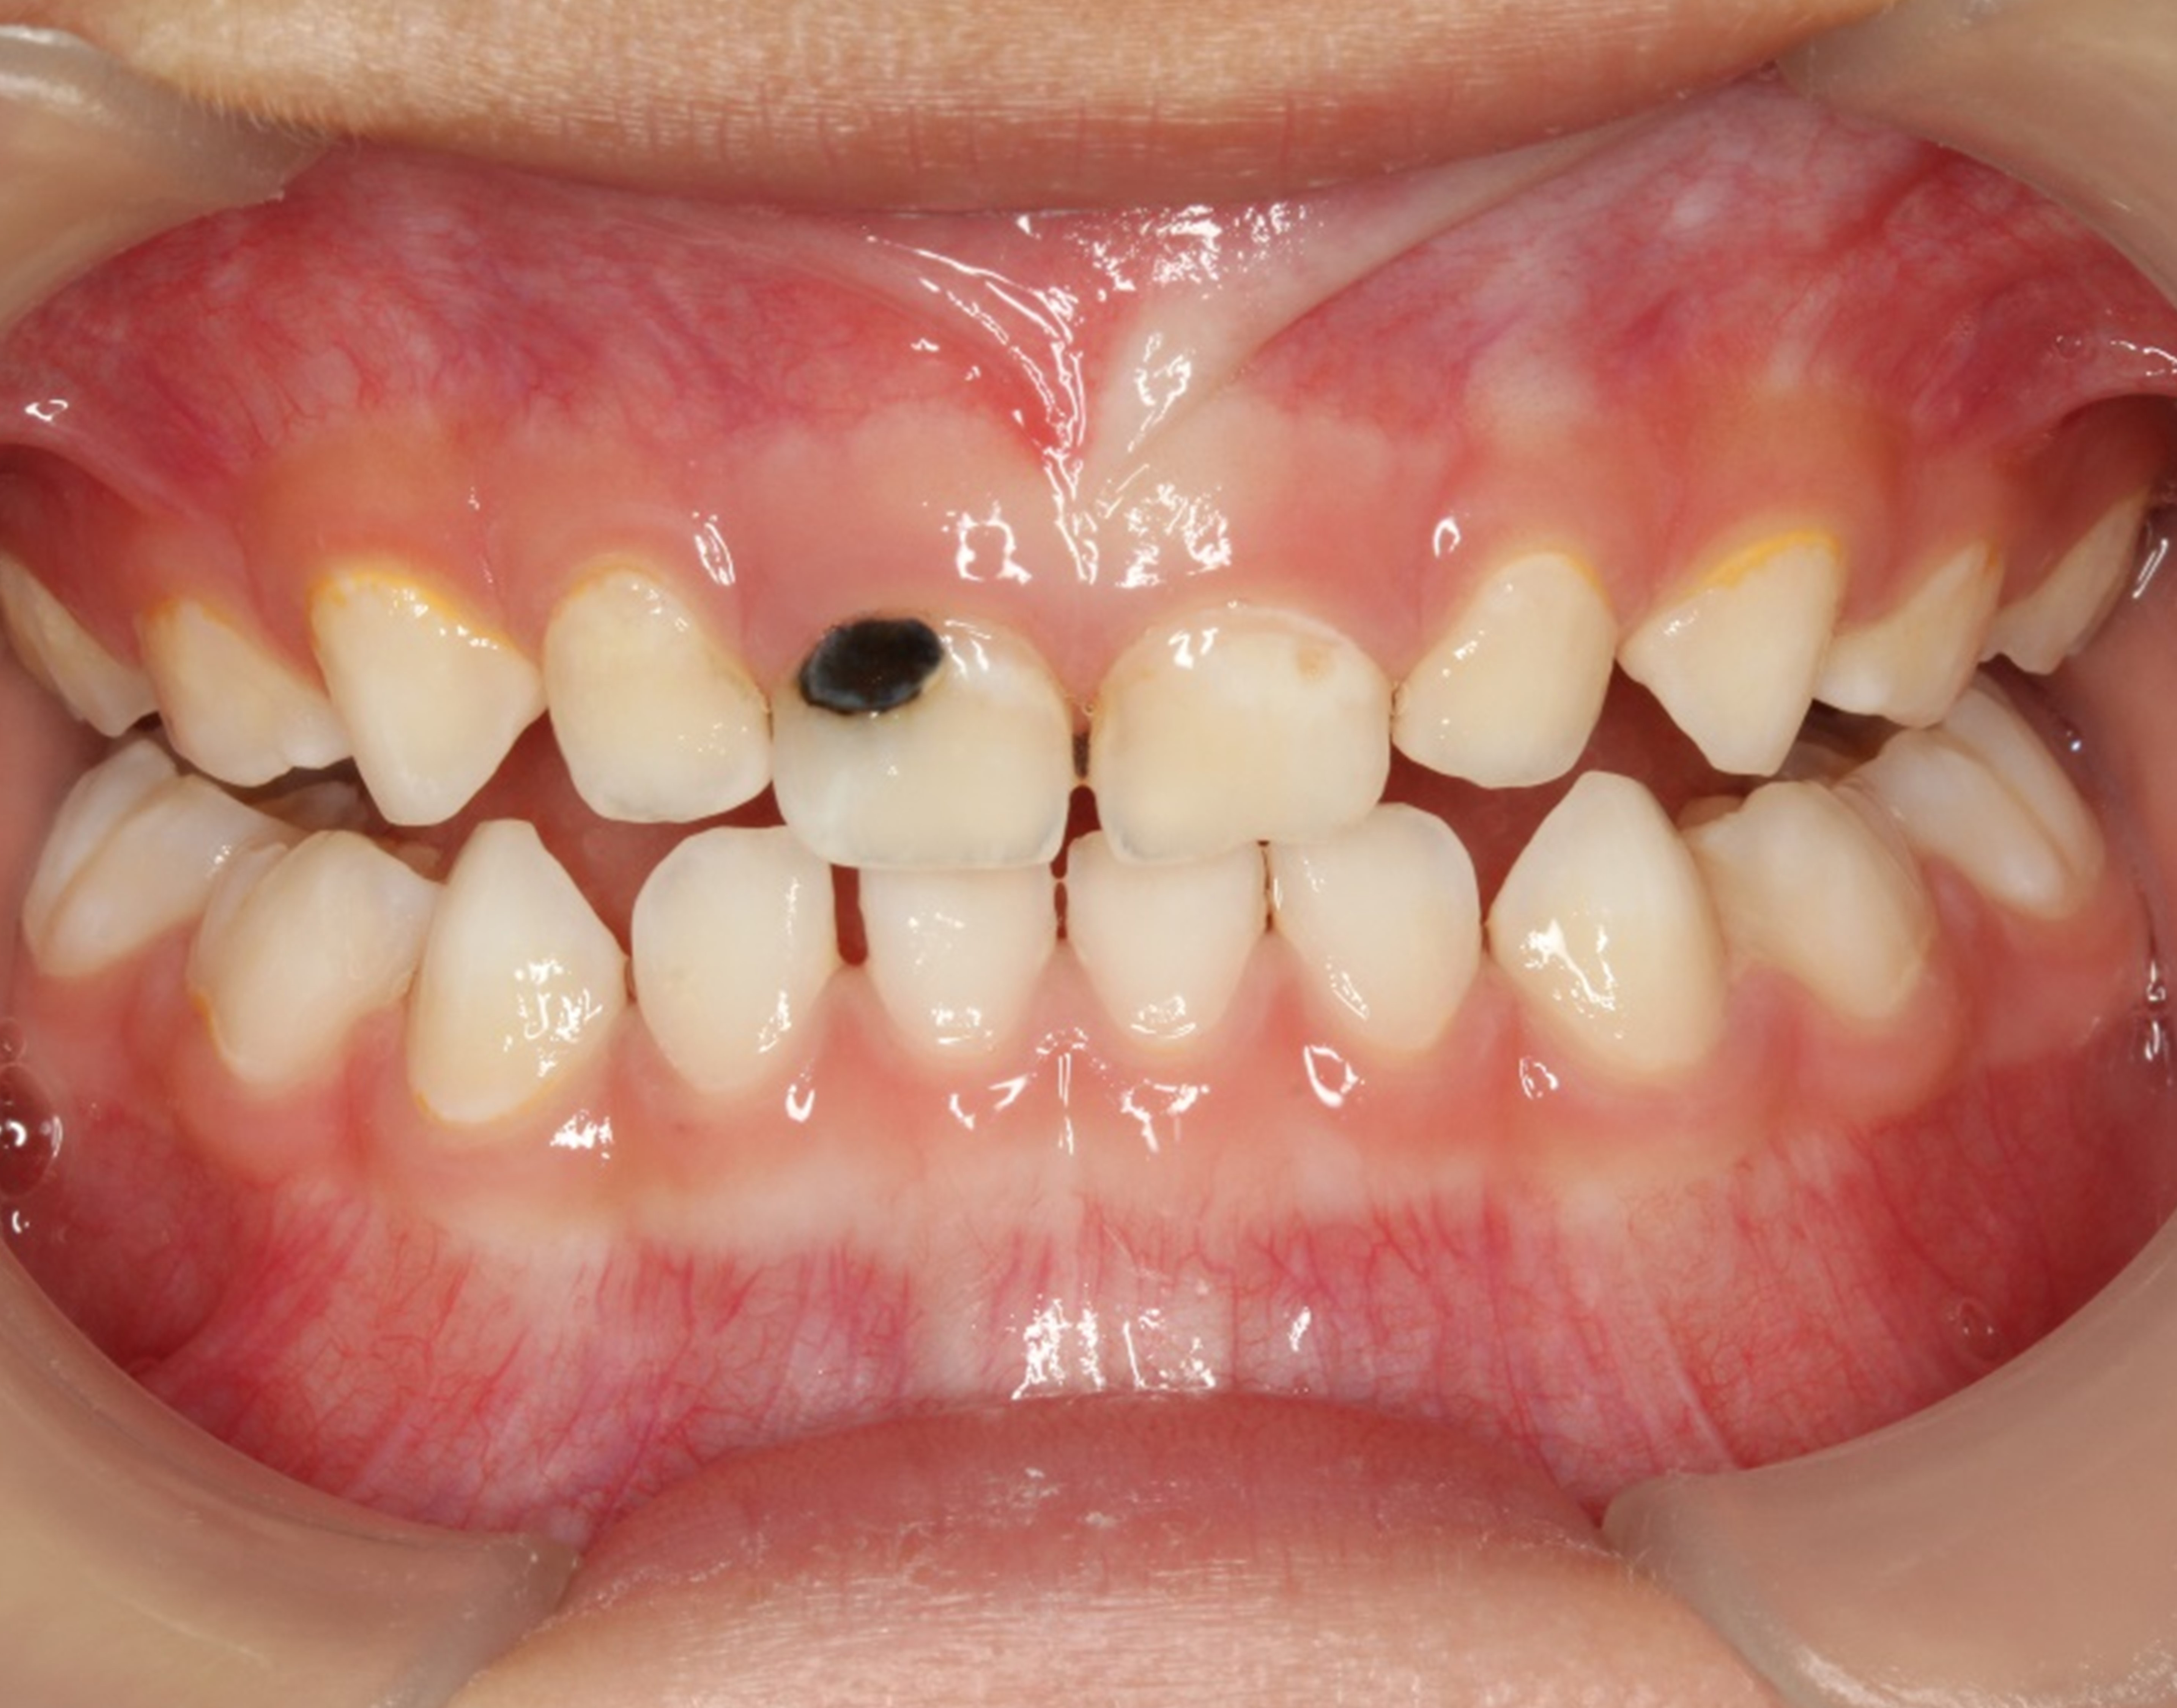

There are several advantages of using SDF in dental treatment. First, it showed an antimicrobial activity against mono-species, dual-species, and multi-species cariogenic biofilm.14-16 Silver ions are bactericidal metal cations that inhibit biofilm formation.17 Studies have indicated that silver interacts with sulfhydryl groups of proteins and DNA, thus altering hydrogen bonding and inhibiting respiratory processes, DNA unwinding, cell-wall synthesis, and cell division.18 At the macro level, these interactions affect bacterial killing and inhibit biofilm formation.17 Second, fluoride promotes caries lesion remineralization. Fluoride has been indicated to react with hydroxyapatite and generate calcium fluoride, which is a reservoir of fluoride, and facilitate further remineralization.19 An ex vivo study reported surface microhardness of the surface layer of the arrested caries after SDF applications was comparable with the unaffected sound dentin20 (Figure 1 and Figure 2). This is consistent with another study, in which a high remineralized zone was observed on the surface of arrested caries from exfoliated teeth with SDF treatment21 (Figure 3 and Figure 4). Third, its application procedures are simple and do not require injection or drilling, and the treatment does not involve expensive support infrastructure equipment such as piped water and electricity. The simplicity of the treatment is conducive to treating caries in apprehensive young children who may have intense dental fear, uncooperative patients with special needs, or elderly patients who have difficulty adapting to traditional dental care. It also allows trained workers to deliver the treatment to people who live in the area but who may not be able to easily access dental service.22 Patient compliance and satisfaction is often good when the patient is provided a clear explanation of the treatment outcome.23,24 Finally, the cost of SDF treatment is low and should be affordable in most communities.

Fig 1. Ground section of a primary incisor with arrested caries lesion after SDF treatment: arrested caries that had SDF treatment. (image from Chu and Lo, 2008, ref 20 [reprinted with approval])

Figure 1